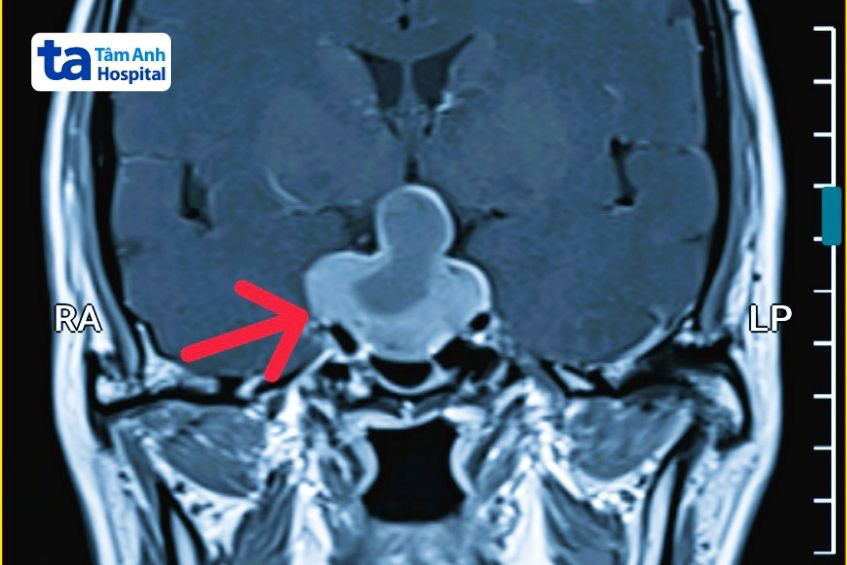

Đơn cử các trường hợp điều trị thành công tại Bệnh viện Tâm Anh. Anh Được, 34 tuổi, khám sức khỏe tổng quát, kết quả chụp MRI 3 Tesla phát hiện khối u tuyến yên khoảng 2 cm. Khối u chiếm trọn diện tích hố yên và trên yên dù trước đó anh Được không khởi phát triệu chứng.

Trường hợp khác là bà Phụng, 51 tuổi, thường xuyên nhìn mờ, đau đầu, chóng mặt. Kết quả chụp MRI 3 Tesla phát hiện khối u tuyến yên kích thước 4 cm, có dấu hiệu xuất huyết, chèn ép lên giao thoa thị và thành xoang hang hai bên.